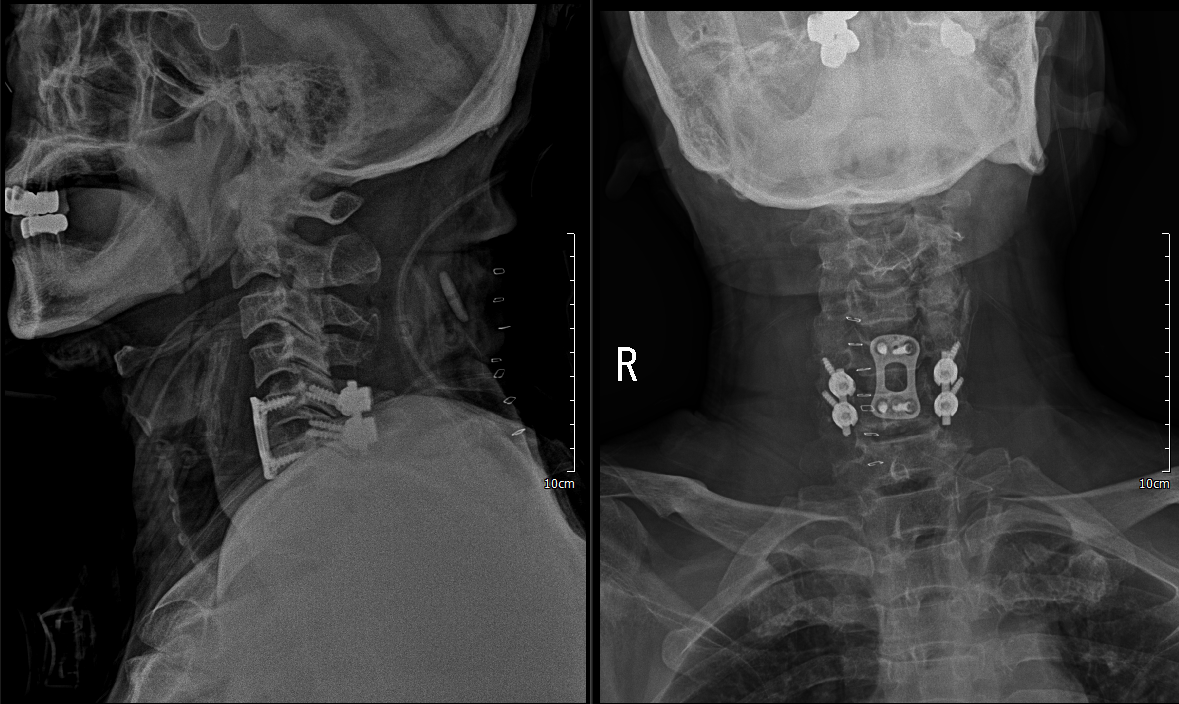

x ray 측면에서 보면 경추 5/6 후관절 탈골이 확인이 됨.

reduction 된 것을 확인 하였음.

1. C5/6 ACDF & iliac bone graft(Rt)

2. PF C5/6

자동차 보험 환자라 cage 및 plate를 둘다 사용할 수 없어서 cage 대신에 우측 iliac bone을 떼서 C5/6 discectomy 이후 넣음

C5/6 ACDF & iliac bone graft(Rt)

하지만 안정성 확보를 위해 5일 후 뒤쪽으로 고정술 시행

lateral mass screw을 사용하여 고정술 시행